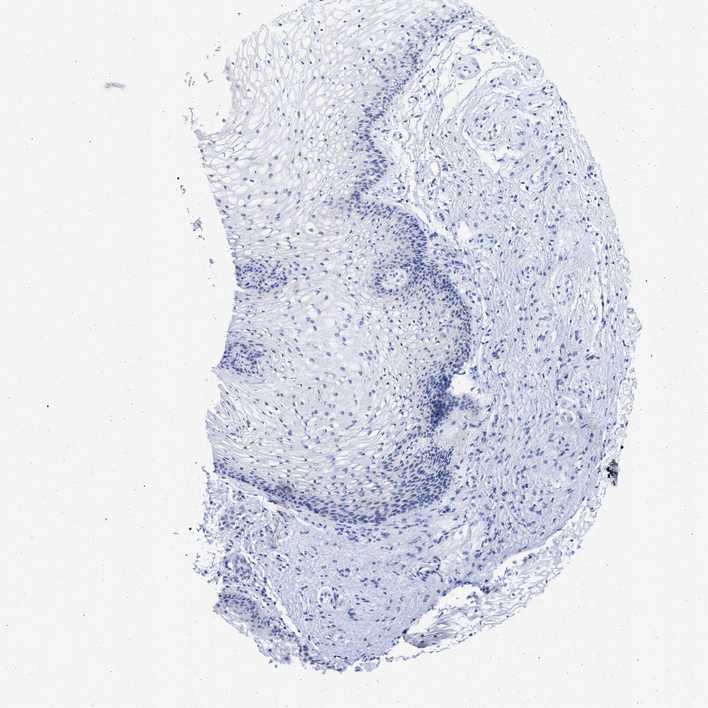

VAGINA - Antibody stainingi

Antibody staining in the annotated cell types in the current human tissue is reported as not detected, low, medium, or high, based on conventional immunohistochemistry profiling in selected tissues. This score is based on the combination of the staining intensity and fraction of stained cells.

Each image is clickable and will lead to virtual microscopy that enables deeper exploration of all samples and also displays staining intensity scores, fraction scores and subcellular localization as well as patient and tissue information for each sample.

Antibody HPA016816Antibody HPA017382

Squamous epithelial cells Not detectedNot detected